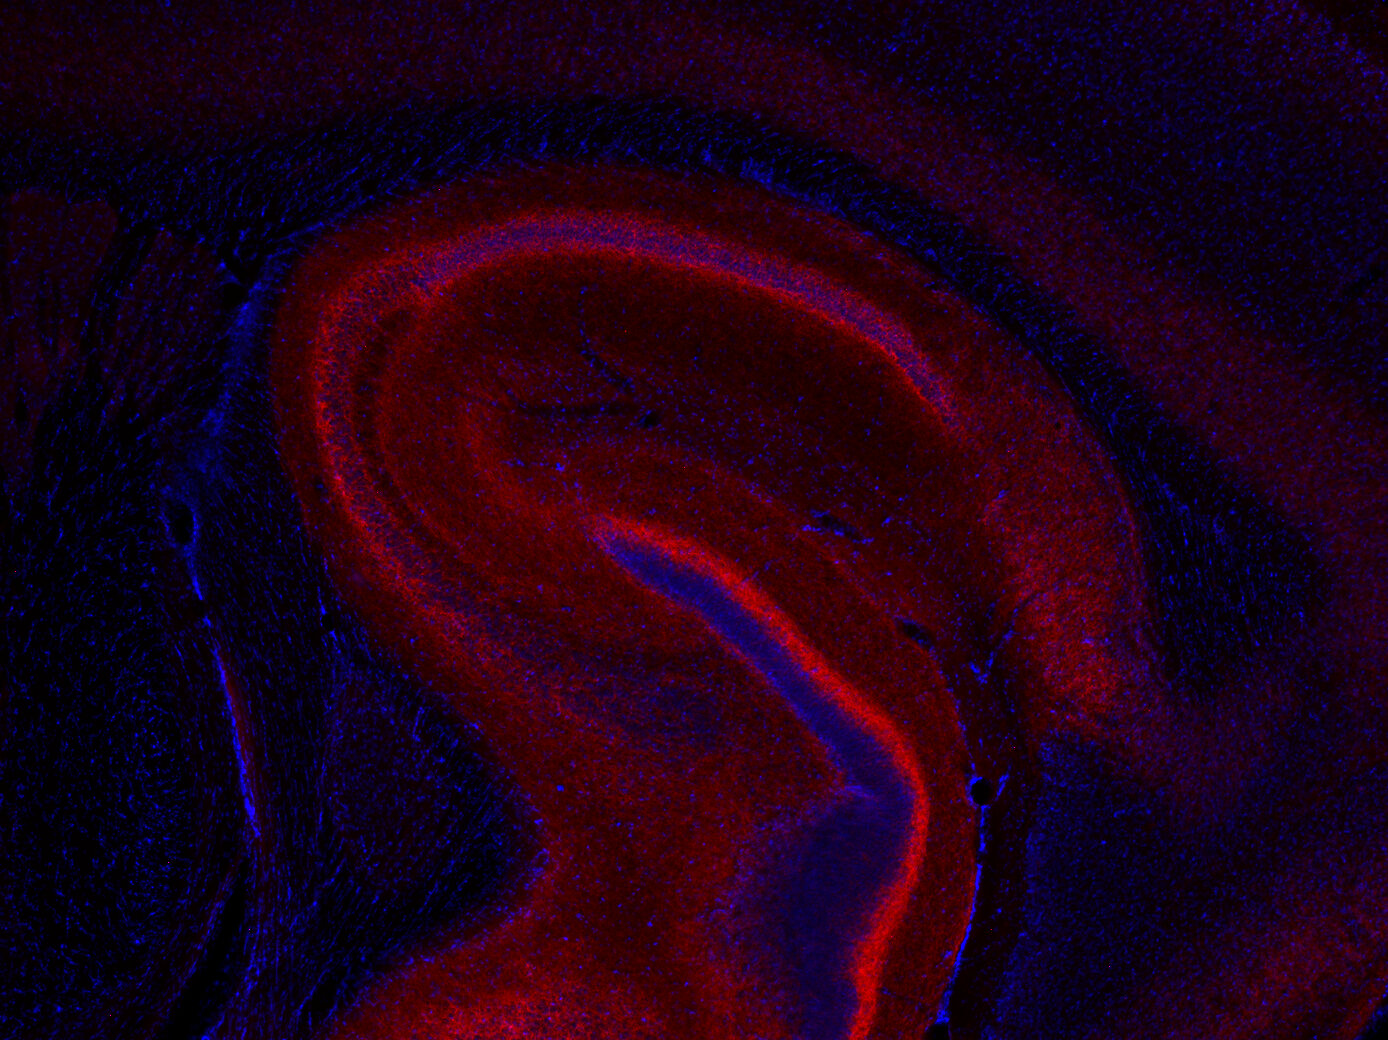

ICC: 1 : 500 gallery

Immunocytochemistry (ICC) on 4% PFA fixed cells. Immunoreactivity is usually revealed by fluorescence. Some antibodies require special fixation methods. For details, please refer to the “Remarks” section.